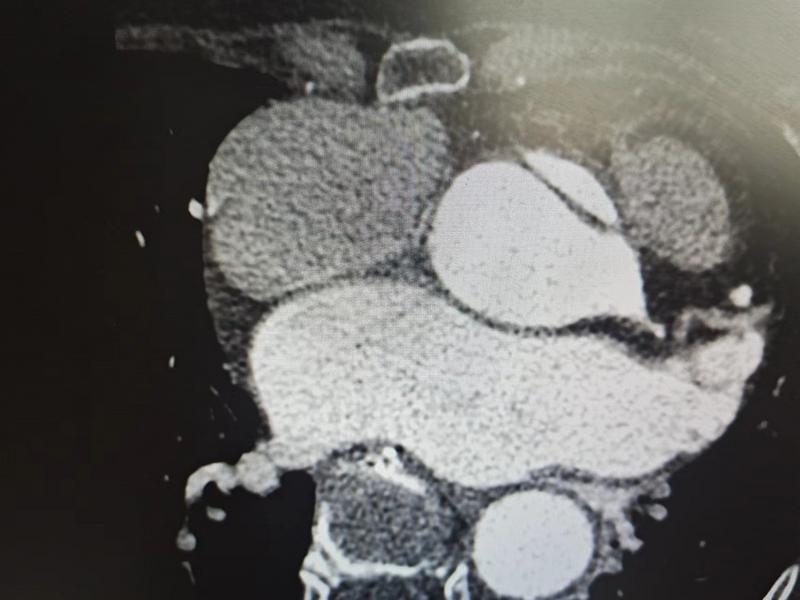

該患者因反復(fù)發(fā)作胸悶、氣喘、心前區(qū)疼痛入住市人民醫(yī)院心內(nèi)科,心臟超聲檢查發(fā)現(xiàn)主動(dòng)脈瓣嚴(yán)重返流伴升主動(dòng)脈夾層動(dòng)脈瘤,后經(jīng)大血管CTA檢查,證實(shí)超聲診斷,左竇上方有一破口,向上撕裂形成假腔。為預(yù)防病情進(jìn)一步加重,在心內(nèi)科主任王岳松的組織下,科室召開病例討論會(huì),研究下一步治療方案。討論結(jié)果一致認(rèn)為必須采取內(nèi)科介入或外科手術(shù)治療。由于患者年齡較大,兩種治療方案均存在較高風(fēng)險(xiǎn),外科開胸進(jìn)行主動(dòng)脈和升主動(dòng)脈置換,手術(shù)復(fù)雜且創(chuàng)傷大,風(fēng)險(xiǎn)更高;如果采取經(jīng)皮主動(dòng)脈瓣置換,創(chuàng)傷小、用時(shí)短,雖然術(shù)中有誘發(fā)夾層破裂的可能,但只要規(guī)范操作,總體風(fēng)險(xiǎn)可控。在告知患者及家屬兩種方案利弊后,患者及家屬選擇內(nèi)科經(jīng)皮瓣膜置換法。為慎重起見,心內(nèi)科團(tuán)隊(duì)再次組織全院相關(guān)科室及皖醫(yī)附院湯圣興教授線上交流討論,制定詳細(xì)的介入手術(shù)預(yù)案。介入手術(shù)當(dāng)天,在醫(yī)院麻醉手術(shù)科、ICU、胸心外科等相關(guān)科室配合下,心內(nèi)科團(tuán)隊(duì)在外院專家指導(dǎo)下,成功為該患者實(shí)施經(jīng)皮主動(dòng)脈瓣置換術(shù),手術(shù)非常順利,用時(shí)不到兩小時(shí),術(shù)后復(fù)查造影和心臟超聲,主動(dòng)脈瓣返流及主動(dòng)脈夾層基本消失,患者及家屬對(duì)醫(yī)院醫(yī)療技術(shù)和服務(wù)能力給予了很高評(píng)價(jià)。

CT夾層圖片